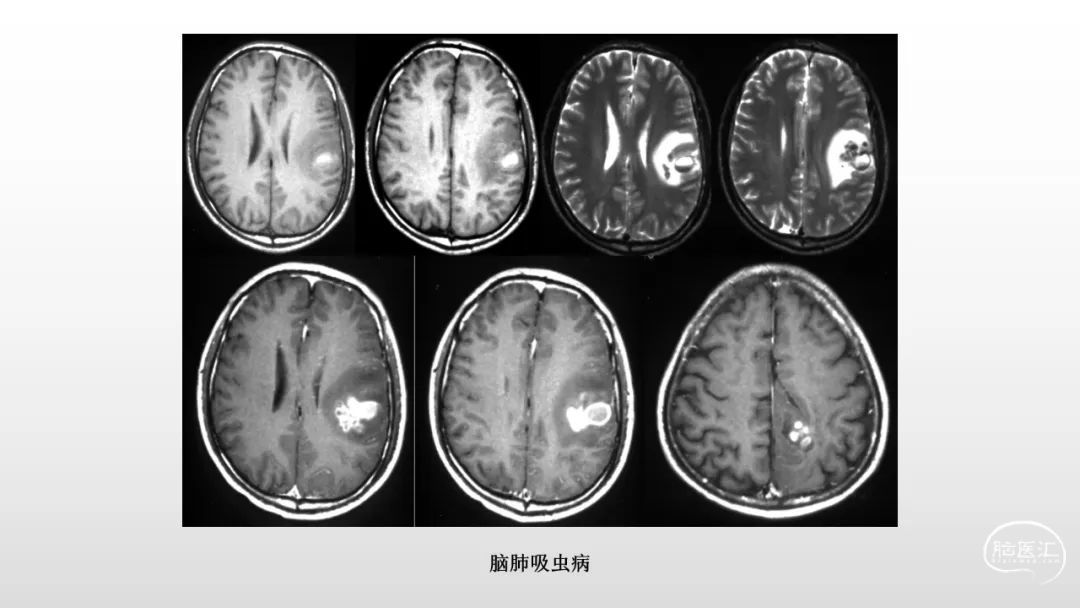

颅脑影像诊断基础知识讲座:感染和免疫性疾病1